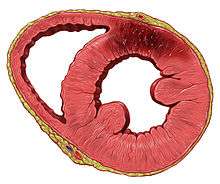

Acute myocardial infarction refers to two subtypes of acute coronary syndrome, namely non-ST-elevated and ST-elevated MIs, which are most frequently (but not always) a manifestation of coronary artery disease.[54] The most common triggering event is the disruption of an atherosclerotic plaque in an epicardial coronary artery, which leads to a clotting cascade, sometimes resulting in total occlusion of the artery.[55][56] Atherosclerosis is the gradual buildup of cholesterol and fibrous tissue in plaques in the wall of arteries (in this case, the coronary arteries), typically over decades.[57] Bloodstream column irregularities visible on angiography reflect artery lumen narrowing as a result of decades of advancing atherosclerosis.[58] Plaques can become unstable, rupture, and additionally promote the formation of a blood clot that occludes the artery; this can occur in minutes. When a severe enough plaque rupture occurs in the coronary arteries, it leads to MI (necrosis of downstream myocardium).[55][56] It is estimated that one billion cardiac cells are lost in a typical MI.[59]

If impaired blood flow to the heart lasts long enough, it triggers a process called the ischemic cascade; the heart cells in the territory of the occluded coronary artery die (chiefly through necrosis) and do not grow back. A collagen scar forms in their place. Recent studies indicate that another form of cell death, apoptosis, also plays a role in the process of tissue damage following an MI.[60] As a result, the person's heart will be permanently damaged. This myocardial scarring also puts the person at risk for potentially life-threatening abnormal heart rhythms (arrhythmias) and may result in the formation of a ventricular aneurysm that can rupture with catastrophic consequences.

Pathological types

The two main types of acute myocardial infarction, based on pathology, are:

- Transmural AMI is associated with atherosclerosis involving a major coronary artery. It can be subclassified into anterior, posterior, inferior, lateral, or septal. Transmural infarcts extend through the whole thickness of the heart muscle and are usually a result of complete occlusion of the area's blood supply.[68] In addition, on ECG, ST elevation and Q waves are seen.

- Subendocardial AMI involves a small area in the subendocardial wall of the left ventricle, ventricular septum, or papillary muscles. The subendocardial area is particularly susceptible to ischemia.[68] In addition, ST depression may be seen on ECG in addition to T wave changes.